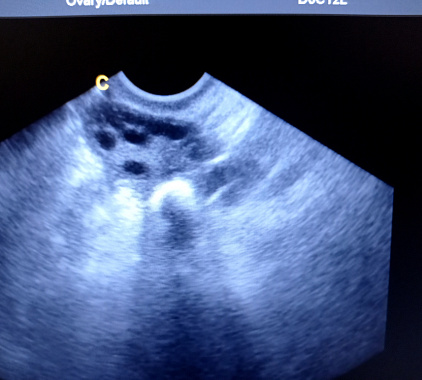

- Врач через влагалище устанавливает датчик УЗИ и оценивает исходное состояние матки, яичников, эндометрия.

- Затем через шейку матки аккуратно вводит тонкий катетер небольшого диаметра (обычно это мягкий проводник). Посредством катетера вводят физиологический раствор или жидкость контрастного типа– она заполняет полость матки и дальше проходит в трубы. На экране врач видит процесс заполнения: как контраст движется по трубам и выходит ли в брюшную полость.

В заключении указывают, что удалось оценить и какие результаты получены. На практике ультразвуковая диагностика маточных труб отвечает на два главных вопроса: есть ли проход и на каком участке может быть препятствие.

Что показывает УЗИ в норме:

- контраст или раствор свободно заполняет полость матки и затем проходит по обеим трубам;

- видно поступление жидкости в брюшную полость с обеих сторон (признак проходимости);

- полость матки без выраженного патологического «рельефа», эндометрий соответствует дню цикла;

- нет признаков выраженного воспаления, грубых деформаций стенки.

Фотогалерея

Оборудование УЗИ